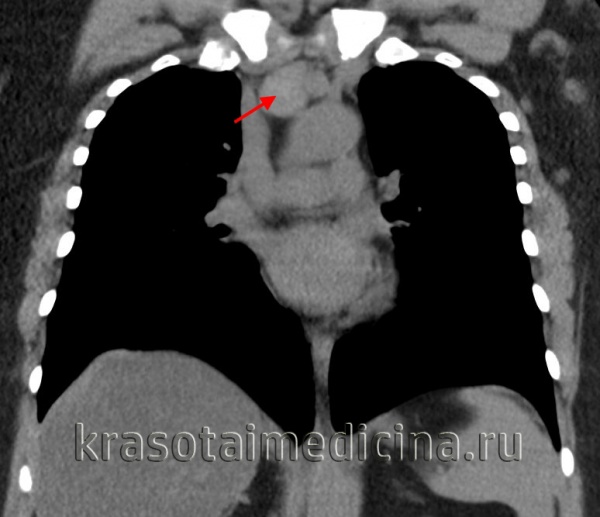

(б) При ФДГ-ПЭТ/КТ в левой стенке трахеи визуализируется объемное образование, интенсивно поглощающее ФДГ. При бронхоскопической биопсии был выявлен плоскоклеточный рак. (а) У пациента с жалобами на хронический кашель при рентгенографии органов грудной клетки в ПП проекции вдоль правой стенки трахеи над верхней апертурой грудной клетки определяется опухолевидное затемнение.

(б) У этого же пациента при КТ с контрастным усилением визуализируется мягкотканное объемное образование, прорастающее правую и заднюю стенки трахеи и распространяющееся на прилежащие отделы средостения. При бронхоскопической биопсии был выявлен плоскоклеточный рак. Распространение опухоли на прилежащие отделы средостения свидетельствует о ее злокачественности. (а) У пациента с аденоидно-кистозной карциномой при КТ с контрастным усилением определяется циркулярное утолщение стенки верхних отделов трахеи. Некоторые новообразования трахеи и бронхов, например аденоидно-кистозная карцинома, могут проявляться утолщением стенки, а не объемным образованием в просвете.